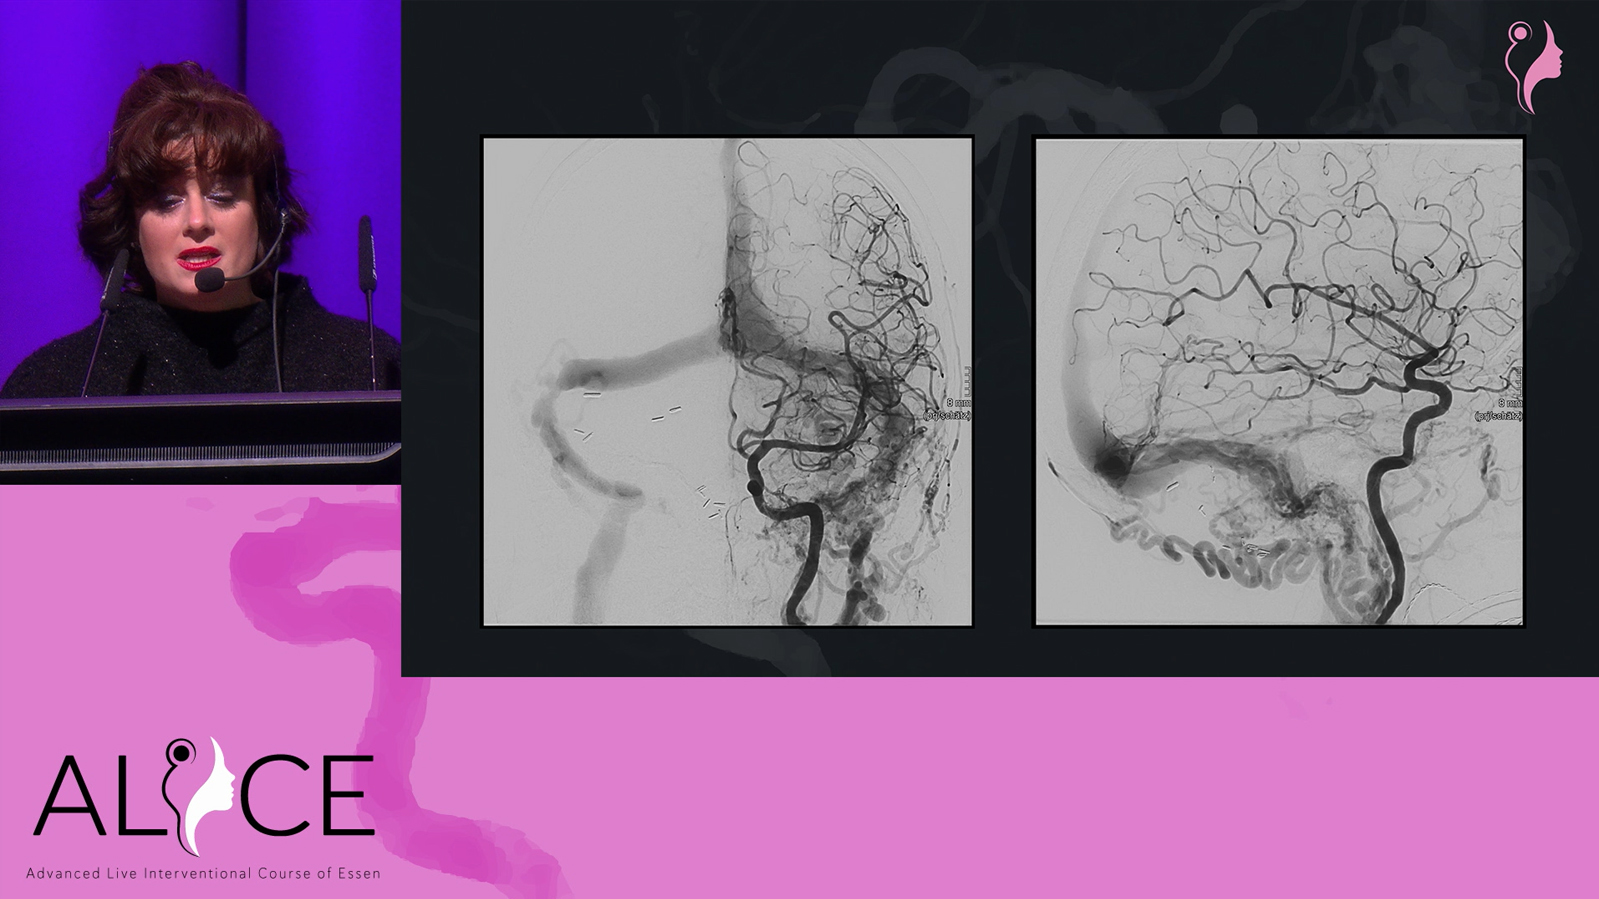

Remnant after first embolization of a temporal AVM to be treated by venous approach

Temporal AVM treated by combined transarterial and transvenous embolization